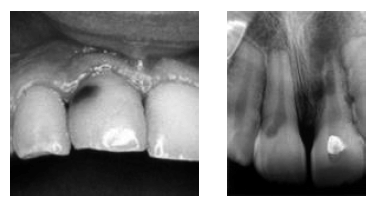

Determinada paciente adulta procurou atendimento odontológico por apresentar mancha escura no dente anterior superior. Ela relatou que, quando era criança, havia sofrido um acidente de bicicleta que lhe provocara trauma nos dentes anteriores. O exame clínico revelou que o incisivo central superior direito apresentava alteração cromática sem cavitação, e o exame radiográfico evidenciou reabsorção interna, conforme mostrado respectivamente nas seguintes imagens.

Acerca dos múltiplos aspectos relacionados a esse caso clínico, julgue os itens que se seguem.